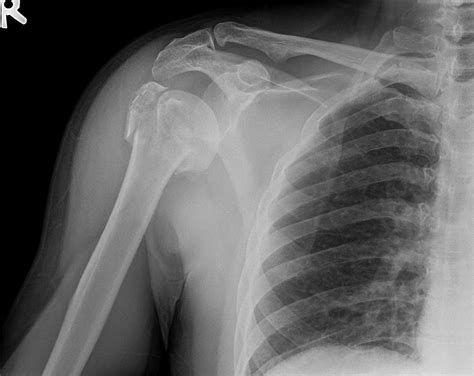

Diagnosing Proximal Humerus Fractures

Diagnosing a proximal humerus fracture involves a combination of physical examination and imaging tests. The diagnostic process typically includes:

• Imaging Tests: X-rays are the primary imaging tool used to diagnose proximal humerus fractures. In some cases, additional tests such as CT scans or MRIs may be ordered to provide more detailed images.